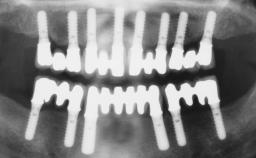

Transition from an “irrational to treat” Maxillary Dentition to a Full-Arch Segmented FDP by Early Loading of Eight Implants Placed Using the Staged Approach

The staged approach permits the transition from an “irrational to treat”dentition to a full arch implant supported restoration without any need to use a removable provisional prosthesis or to apply the immediate-placement and immediate-loading techniques.  A failing dentition is the usual indication for a staged treatment. On the other hand, the dentition should still contain many residual teeth, but with few or none of them being suitable for use as definitive abutments for a full-arch fixed restoration.This situation is usually the result of advanced periodontal disease or of the failure of an extensive fixed prosthesis.

# of Implants 8

Type of Implants One-Piece

Bone Augmentation Horizontal|Simultaneous

Defining Characteristics Fully edentulous upper jaw to be rehabilitated with four or more implants

Bone Volume Deficient horizontally, allowing simultaneous augumentation